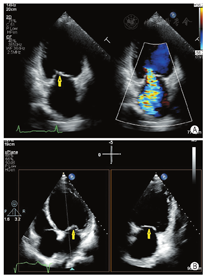

通过采集4个食管中段切面完整显示二尖瓣(图8)。①食管中段的四腔心切面:显示A2、A3和P1;②食管中段的二尖瓣交界处切面:显示A2、P1和P3;③食管中段的二腔心切面:显示A1、A2和P3;④食管中段的长轴切面:显示A2和P2。

MR介入治疗术前和术中,经常使用三维TEE的X-plane双切面(包括二尖瓣交界处二腔心切面及三腔心切面)来评估二尖瓣解剖:二尖瓣交界处二腔心切面能清晰显示二尖瓣后叶P1及P3、前叶A2,而三腔心切面能清晰显示二尖瓣前叶A2、后叶P2。也可通过二尖瓣的"三维外科视野"立体显示二尖瓣前后叶(图9)。

二维、三维TEE通过上述切面评价MR的机制、程度以及部位,并确定瓣膜运动异常的扇区。